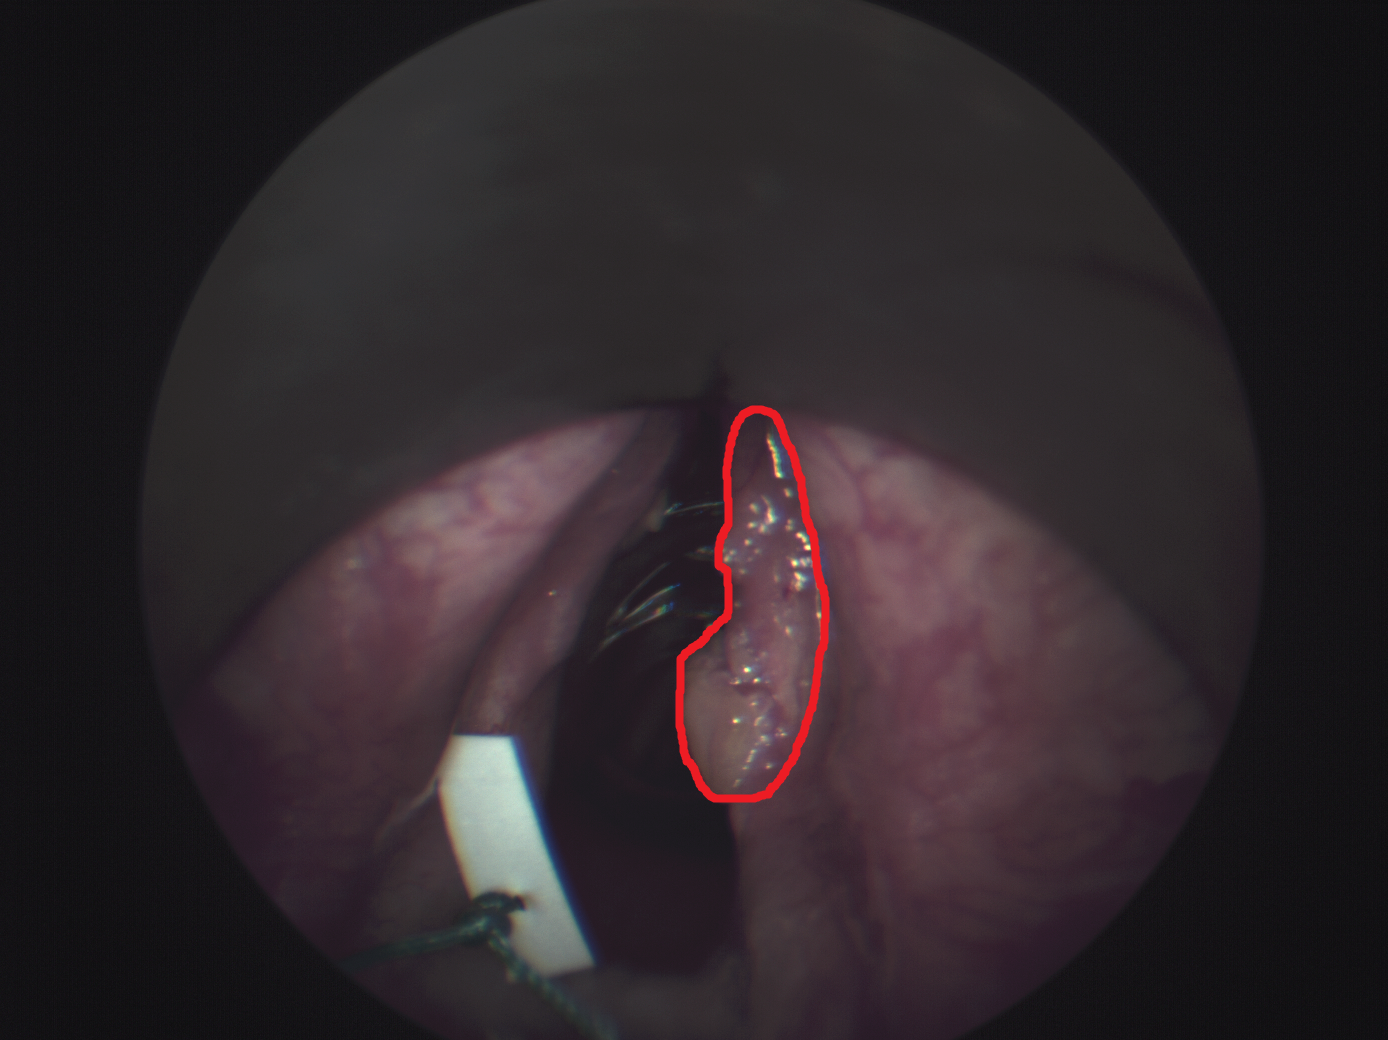

The data set consists of 98 patients, who were examined in a previous study due to mucous membrane abnormalities in the area of the upper aerodigestive tract [3]. Data acquisition was performed as described by Gerstner et al. [8] at the department of otorhinolaryngology at the University of Bonn. The study was approved by the local ethics committee (176/10 & 061/13, University of Bonn). The acquisition was performed throughout a normal procedure for diagnosis. An endoscopic device (Karl Storz GmbH & CoKG, Tuttlingen, Germany) was used for visual assessment. A Polychrome V monochromator (TillPhotonics, Gräfelfing, Germany) was used as light source for HSI and a monochromatic CCD-camera (AxioCamMRm, Carl Zeiss Microimaging GmbH, Göttingen, Germany) was employed for HSI data acquisition. The spectral bands range from to with a step size of and a bandwidth of . The spatial resolution is pixels. Biopsy samples were extracted from the imaged tumor areas, followed by histopathological evaluation. After the acquisition, we use the ImageJ-implementation of the SIFT-algorithm “Linear Stack Alignment with SIFT” [19] for aligning of the HSI images. Experts performed ground-truth annotation using RGB representations derived from the HSI images and the histopathological report. Note that this method induces some label noise as tumor outlines might be slightly inaccurate. In total, there are 83 patients with benign tumor region and 15 patients with malignant tumor region. Thus, the learning problem is particularly challenging due to extreme class imbalance. Tissue regions include the larynx, oropharynx and hypopharynx. Example images and highlighted tumor regions are shown in Figure 1. For model training and evaluation, we crop patches of size from the marked areas, including a margin towards the marked border. Overall, we obtain patches from all patients. For training and evaluation of our models, we define three subsets with a size of 19 patients (5 malignant / 14 benign) each and apply a cross-fold scheme. Note, data from one patient does not appear in different subsets. We split each subset into a test set (3 malignant / 8 benign) and validation set (2 malignant / 6 benign). We perform hyperparameter optimization using grid search on the validation splits and we report performance metrics for the test splits.